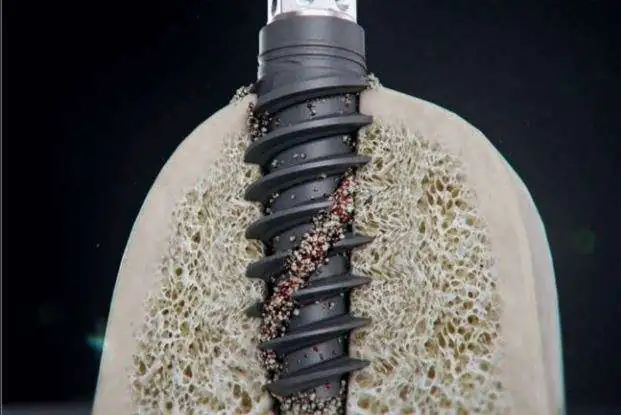

信頼性の高いストローマンSLActiveを使用

患者様の体内に直接埋め込むものは、品質や実績に優れたメーカーのインプラントを選ぶことが重要です。当院では、スイスのストローマン(Straumann)インプラントを採用しています。このメーカーは世界的に高いシェアを誇り、50年以上にわたる研究・開発の歴史を有しています。

患者様の体内に直接埋め込むものは、品質や実績に優れたメーカーのインプラントを選ぶことが重要です。当院では、スイスのストローマン(Straumann)インプラントを採用しています。このメーカーは世界的に高いシェアを誇り、50年以上にわたる研究・開発の歴史を有しています。

信頼性の高いストローマンSLActiveを使用

高い強度と優れた骨結合性を実現

純チタンに、希少金属「ジルコニウム」を配合させた世界で唯一、ストローマン独自の材質です。通常のインプラント体に比べ硬く、咀嚼などで過度に負担がかかった場合に折れるなどのリスクの軽減が望めます。また、高強度な分、インプラント自体を補足設計できるため、比較的骨の薄い前歯に最適で、骨量の心配な方であってもインプラント治療が可能となるケースが広がります。

純チタンに、希少金属「ジルコニウム」を配合させた世界で唯一、ストローマン独自の材質です。通常のインプラント体に比べ硬く、咀嚼などで過度に負担がかかった場合に折れるなどのリスクの軽減が望めます。また、高強度な分、インプラント自体を補足設計できるため、比較的骨の薄い前歯に最適で、骨量の心配な方であってもインプラント治療が可能となるケースが広がります。

骨と結合しやすい構造で治療期間を短縮

最新鋭の技術をもって生み出された次世代のインプラントです。独自の表面性状が骨結合を促し一般的には数ヶ月かかる治癒期間を最短で5~6週間ほどまで早め、さらに従来よりも脱落のリスクを下げることが可能になりました。

最新鋭の技術をもって生み出された次世代のインプラントです。独自の表面性状が骨結合を促し一般的には数ヶ月かかる治癒期間を最短で5~6週間ほどまで早め、さらに従来よりも脱落のリスクを下げることが可能になりました。

世界トップクラスのシェア率

ストローマンインプラントは、世界70ヵ国以上、500万人以上の患者様の治療にしようされている世界シェアNO.1 のインプラントです。45年以上の歴史があり治療後5年及び10年の長期的な臨床データから確かな安全性が立証されているので、安心してお使いいただけます。

ストローマンインプラントは、世界70ヵ国以上、500万人以上の患者様の治療にしようされている世界シェアNO.1 のインプラントです。45年以上の歴史があり治療後5年及び10年の長期的な臨床データから確かな安全性が立証されているので、安心してお使いいただけます。